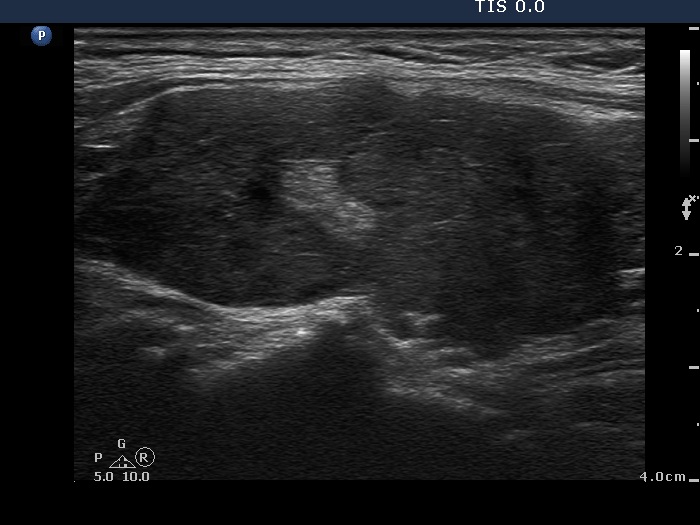

Ultrasonography: The right lobe was hypoechogenic, the left was moderately hypoechogenic. Both lobes were irregular in shape and were composed of several circumscribed areas surrounded with echonormal rim. The vascularization was significantly increased.

The sonographic pattern is specific. At first sight both lobes, particularly the right one seems to be nodular. First, the lobes are composed of a central hypoechogenic part surrounded with an echonormal rim, therefore it seems like the lobes were composed of a large hypoechogenic nodule. Second, connective tissue, perhaps a scar makes an impression in the ventral and in the dorsal part of the right and the left lobe, respectively. This makes an appearance as the lobes were composed of two nodules or one lesion with irregular lobulated and spiculated margins. In fact, the scar is responsible for the irregularities seen on the surface of the hypoechogenic mass, and regarding the hypoechogenic mass, the inclinations are the primary cause.